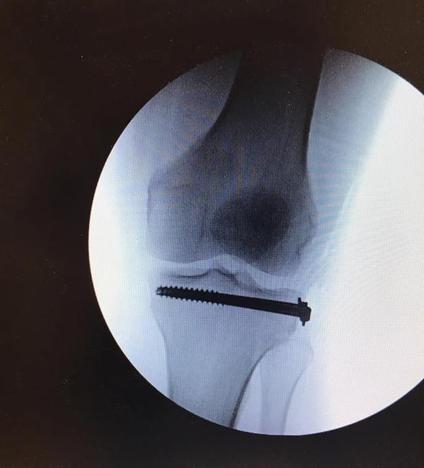

We have a man down here in the GrabCAD office. Our Director of Products and Support, Grant, was recently injured playing ultimate frisbee. He fractured his tibia and has been on crutches for the past two months relying on his colleagues and friends to assist with carrying items for him. After speaking with Grant he shared his obstacles of using crutches. The most irritating one of all was trying to carry food and/or a drink from the kitchen to his desk or while at home. We thought of a great idea to make this into a Challenge and leave it up to the Community to design two accessories he can attach to the crutch to carry his food and a drink without spilling.